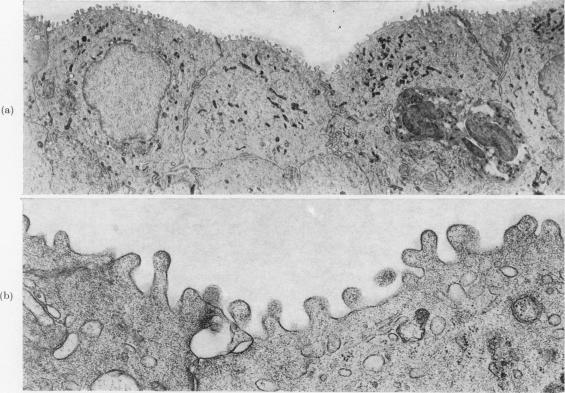

The widely held belief that 2-naphthylamine is not carcinogenic for the rat has been re-examined. Twenty female Wistar rats were dosed by gastric intubation weekly for 57 weeks with 2-naphthylamine, 300 mg/kg body wt, in arachis oil and 20 controls were given arachis oil alone. Animals which became moribund were killed during the course of the experiment and the remainder after 100 weeks. A 2-naphthylamine-treated animal died at 21 weeks; all others survived 57 weeks or longer. The urinary tracts of all but two 2-naphthylamine-treated animals, which were found dead and cannibalized, were examined histologically.No neoplastic disease of the urinary tract was present in control animals. In 10 of the 2-naphthylamine-treated rats there was neither neoplasia nor hyperplasia of the urothelium, but 4 of the 18 examined histologically had large, macroscopically visible bladder cancers; one of these also had bilateral transitional cell tumours of the kidney calyces and multiple tumours in both ureters. Another animal had bilateral urothelial cancers in the ureters. The histology and ultrastructure of these urothelial cancers were comparable to those of rat transitional-cell carcinomas experimentally induced with other chemical carcinogens.These results, considered in the context both of early and more recently published biochemical studies of 2-naphthylamine metabolism in the rat, support the possibility that production of the active carcinogenic metabolite in this species may be influenced by a pH-dependent, non-enzymic mechanism in the urine, which could account for individual, strain- and diet-related variations in response in the rat.